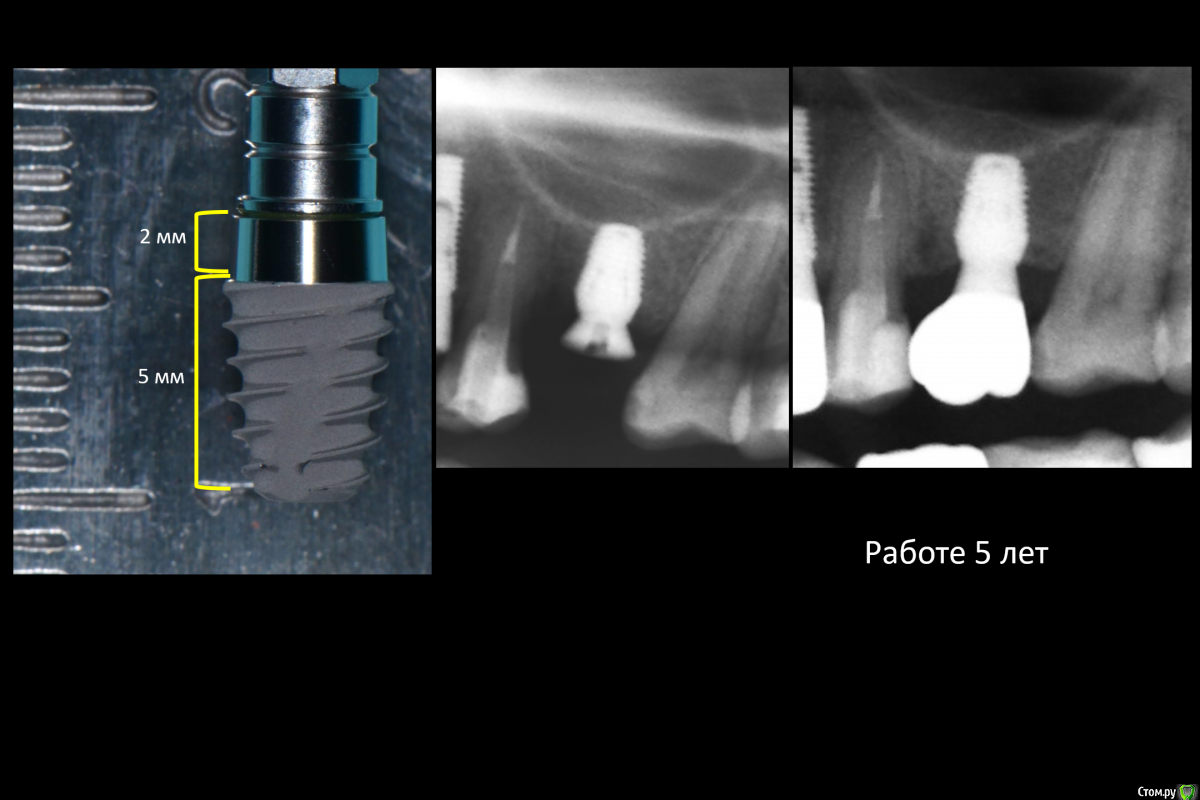

It'sGeorgy Опубликовано 18 февраля, 2021 Поделиться Опубликовано 18 февраля, 2021 В прошлом году начал использовать Tissue Level 6мм Штраумянский. Часто выручает в дистальный отделах НЧ. На ВЧ не использую почти, одиночными - тоже нет. Основной момент: При выраженной вертикальной атрофии, тонкой десне и невозможности редукции, нужно уметь получать мобилизацию лоскутов. У Томаса в главе про Tent pole это описано. Ну и то, что у фрез Штраумановских острый кончик, который выступает на 0.4мм, т.е сверля ложе на 4мм, вы, по факту, будете сверлить на 4.4мм.В остальном, считаю это лучшим вариантом для коротких имплантатов, ибо соединение имплантат-абатмент смещено от кости. Опыт использования положительный, даже в одиночных молярах.4мм на одиночные тоже ставили? 1 Ссылка на комментарий

Snow Doc Опубликовано 25 февраля, 2021 Поделиться Опубликовано 25 февраля, 2021 Суперлайн 4.5/5 * 7(у которых 1.5 полированная шейка) стоят несколько лет. Шестимиллиметровые штрауманн стоят. Выручают в нижних семерках частенько. 1 Ссылка на комментарий

TIGER Опубликовано 12 июля, 2023 Поделиться Опубликовано 12 июля, 2023 @Danger главное условие при коротких это замещение каждого зуба отдельным имплантом,и шина(мост) делаю много на 4-6 TL Straumann 1 Ссылка на комментарий